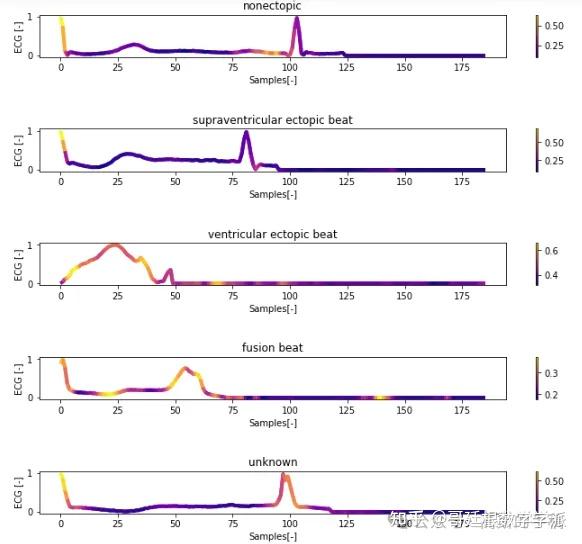

一维神经网络的特征可视化分析-以心电信号为例(Python,Jupyter Notebook)

包括Occlusion sensitivity方法,Saliency map方法,Grad-CAM方法